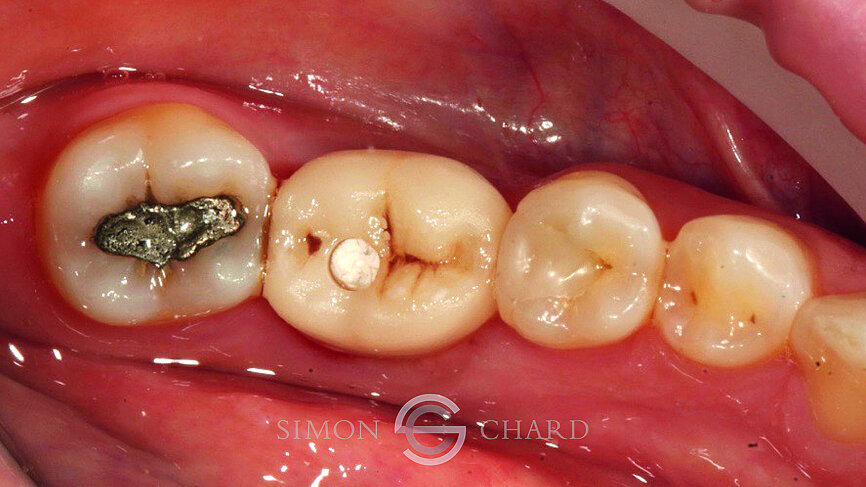

This case report highlights a novel method of restoring implants utilising the modern advances in digital intraoral scanning and chairside milling. It illustrates how an aesthetic single implant retained crown can be provided chairside without the need for analogue impressions (Figs. 1 & 2: Pre-operative condition).

Following 3 months of integration, the patient attended the practice for the restoration of the implant with a definitive crown. During this period, the soft tissue had been given time to mature and a beautiful molar soft tissue profile had formed (Figs. 4 & 5).